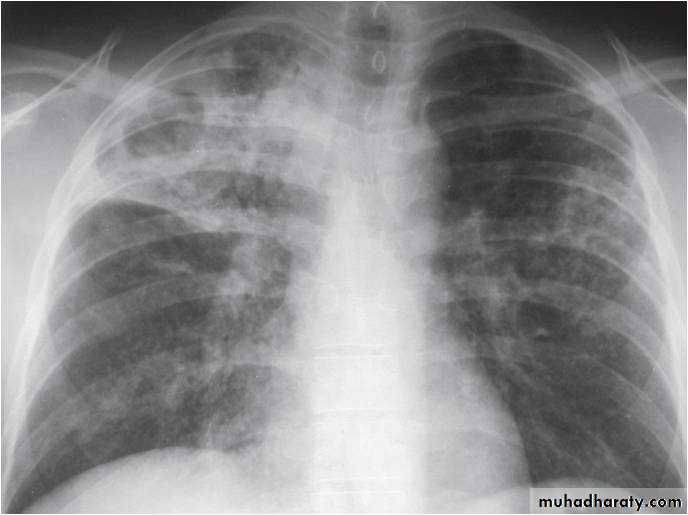

Lobular consolidation ( broncho or lobular pneumoniaCXR of adult ,PA and lateral views show:Patchy consolidation in both lung fields (diffuse) mainly in the lower zonesNormal heart size

Very important to consider that pulmonary edema in normal sized heart have close similar appearance to broncho pneumonia

The important Golden Key differentiation is the cardiac size being enlarged in pulmonary edema .